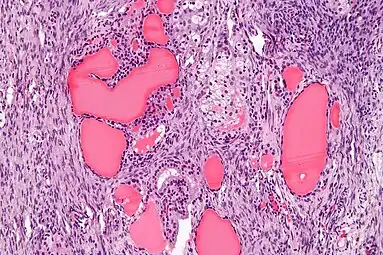

High magnification Struma ovarii